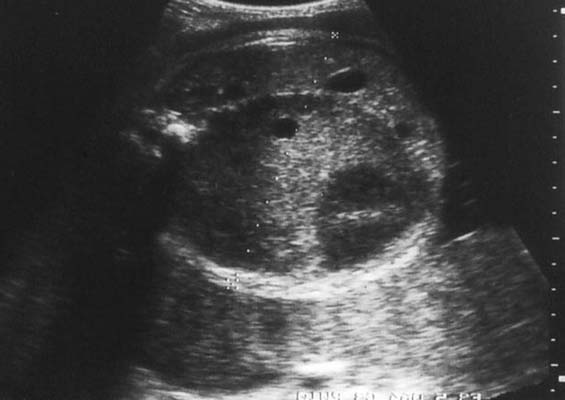

Tumeur de Bolande